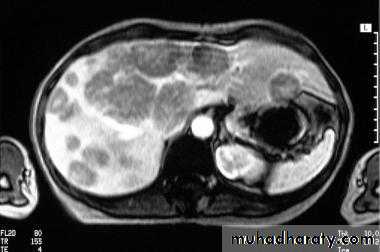

MRI

Malignant neoplasms:

Hemangioma